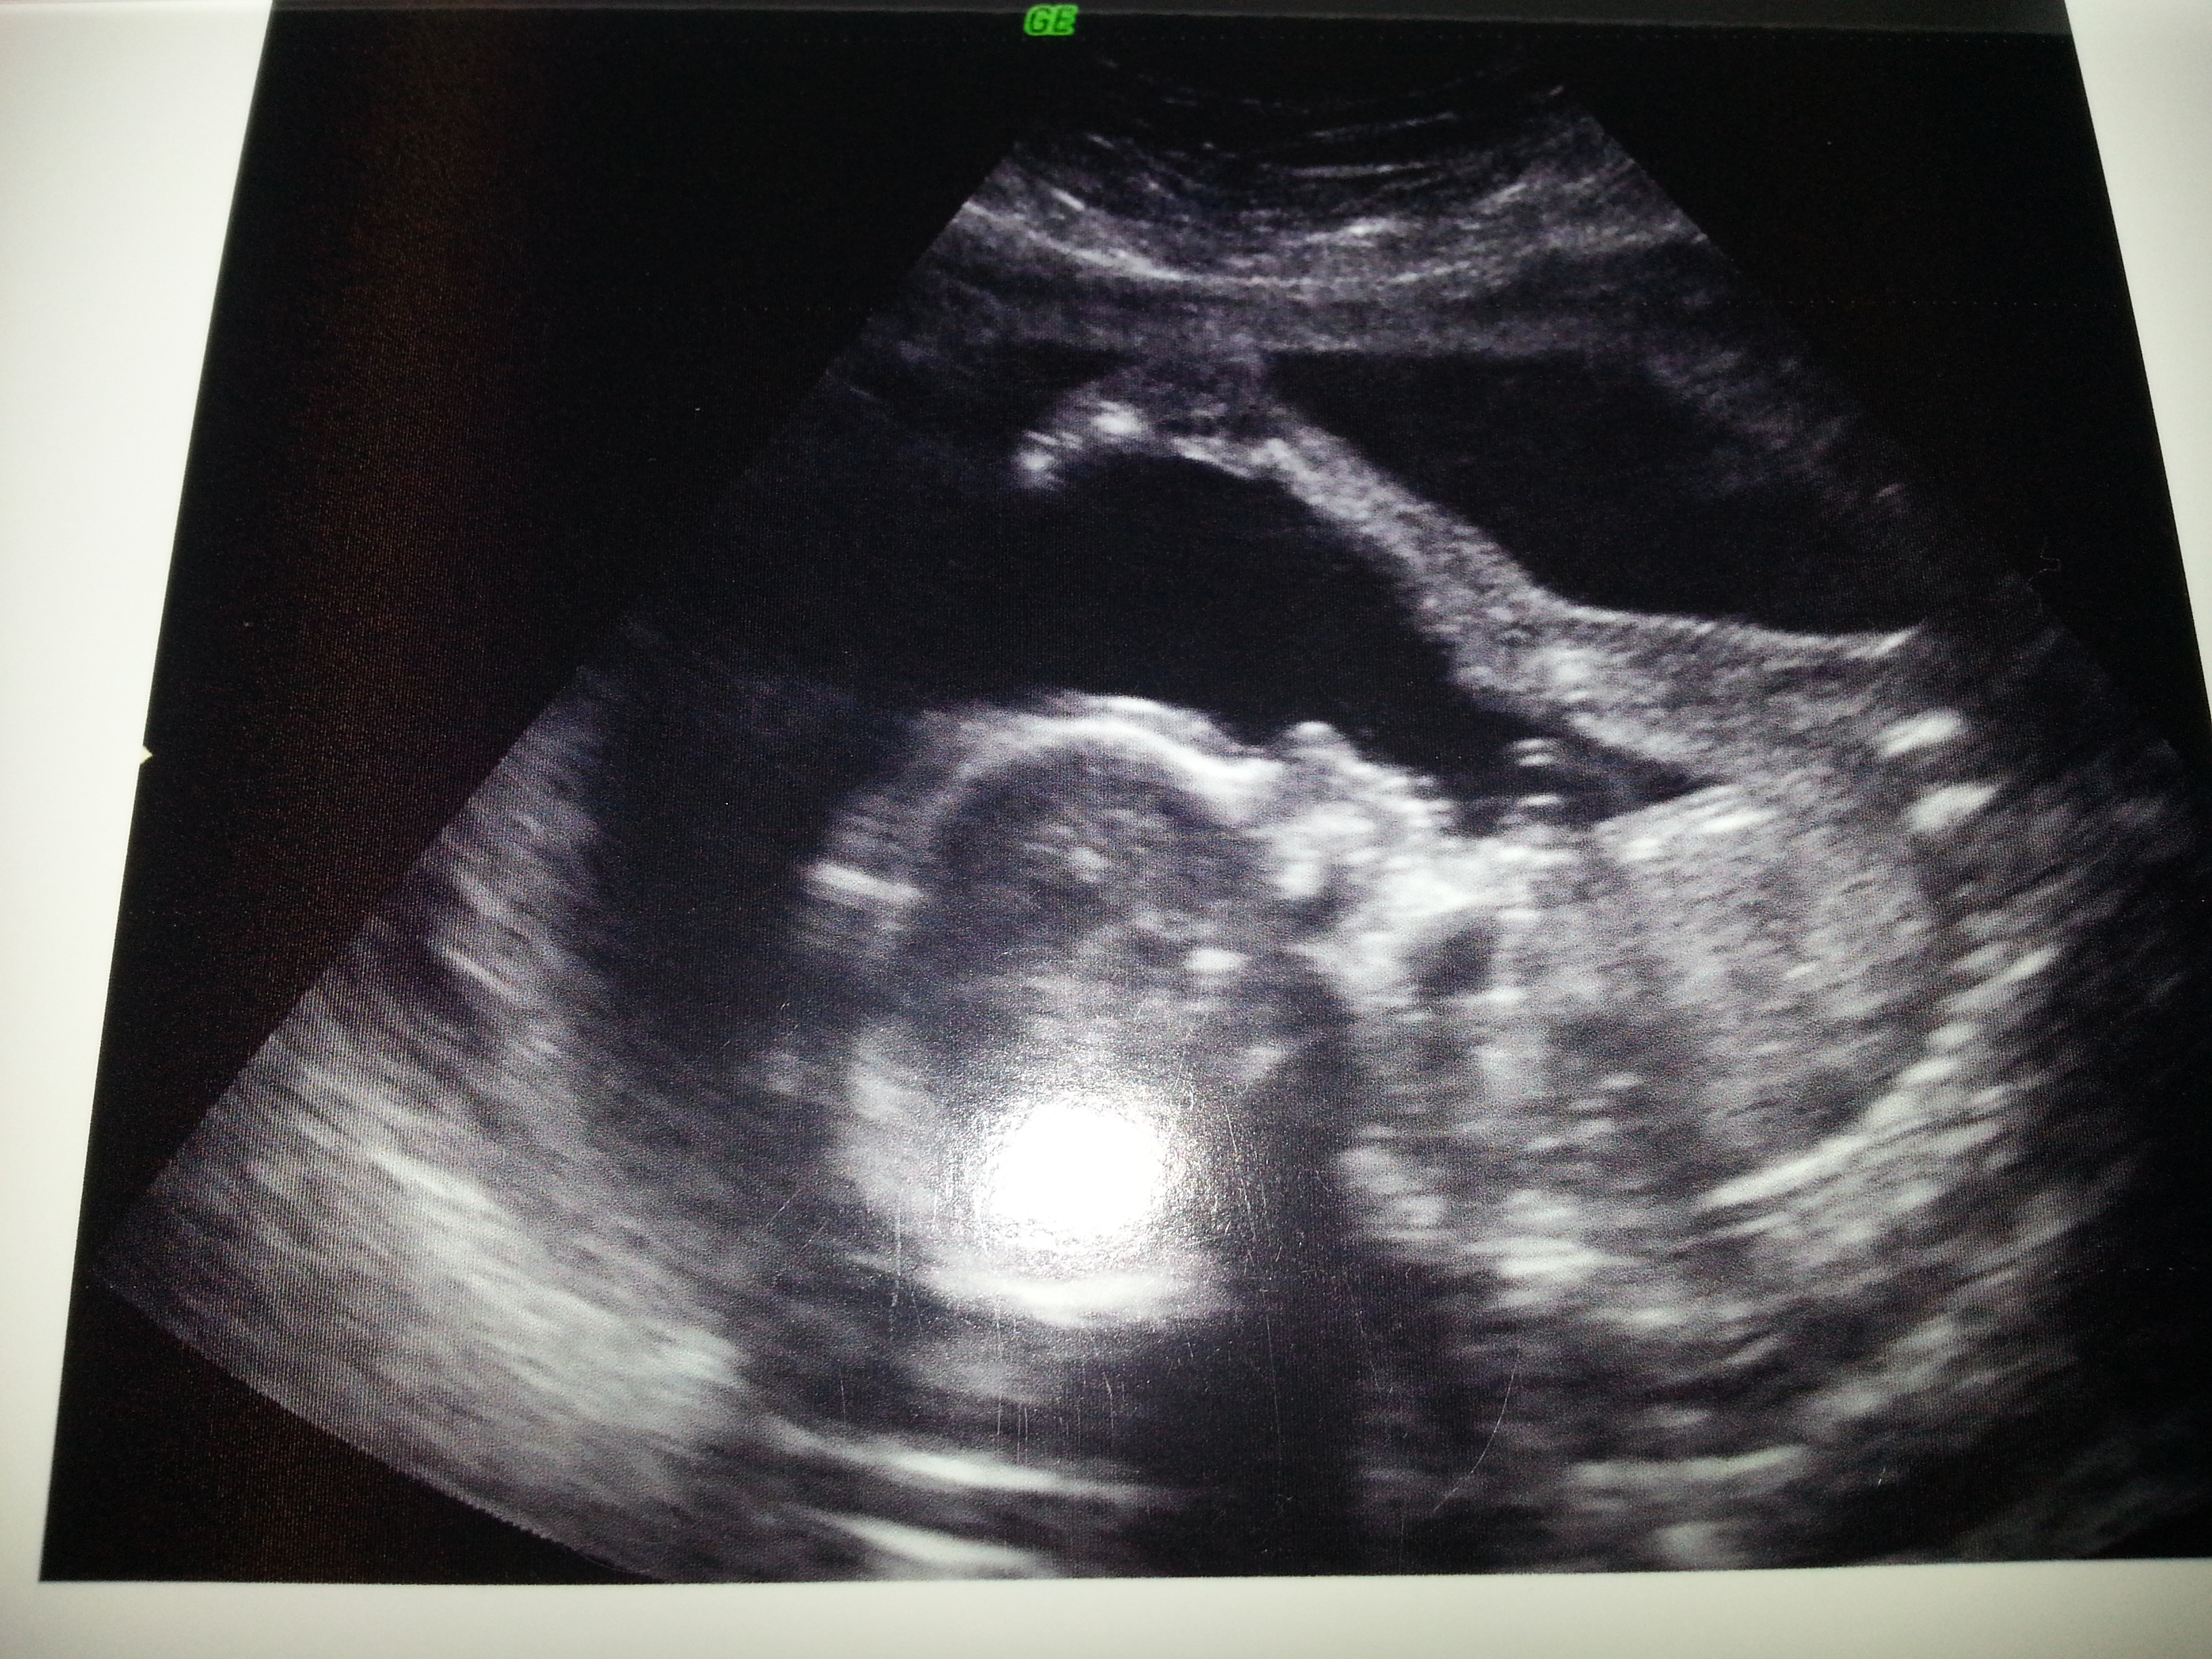

Our daughter E was born 7/29/2012!

Surprise, our 2nd daughter P was born 5/22/14!